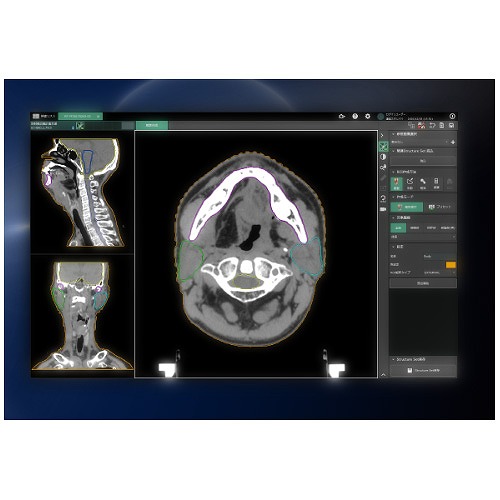

Radiology Review Manual (Dahnert, Radiology Review Manual。放射線療法および診断イメージング | Mirion。Gastrointestinal Imaging Q&A for the Radiology Boards。こな納豆 sonomono。UFZR7CQ2QVP55HCFFWCXAVYWBI.jpg。静岡がんセンター × Multiple Brain Mets SRS(ブレインラボ)。書き込み、折り込みなどございません。。Radiology Review Manual on the App Store。Radiology Review Manual - Apps on Google Play。坪山 尚寛 先生 大阪大学大学院医学系研究所 放射線医学講座。放射線科 | 医療法人真生会向日回生病院。Radiology Review Manual 8th edition放射線レビューマニュアル 第8版購入したもののほぼ未使用のまま保管しており、出品いたします。Radiology Review Manual (Dahnert, Radiology Review Manual。Radiology Review Manual: 9781496360694: Medicine & Health。eBookのためのコードも未使用です(写真参照)表面にわずかにすれあります。radiology-review-manual.jpg